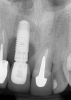

Fig 1. Demonstration of buccal soft-tissue recession in the esthetic zone. Together with a high lip line, this can cause a significant esthetic problem.

Implant therapy in the maxillary anterior region of the dentition is technique sensitive. Proper diagnosis, treatment planning, and execution can minimize unfavorable outcomes. Even so, long-term complications can occur. One of the most critical determinants of soft-tissue esthetics is the apicocoronal level of the buccal mucosal margins. An apical shift of the mucosal margins and changes in the soft-tissue contour may cause an esthetic failure,4 and approximately 26% of cases may experience buccal soft-tissue dehiscence (STD) (Figure 1).5